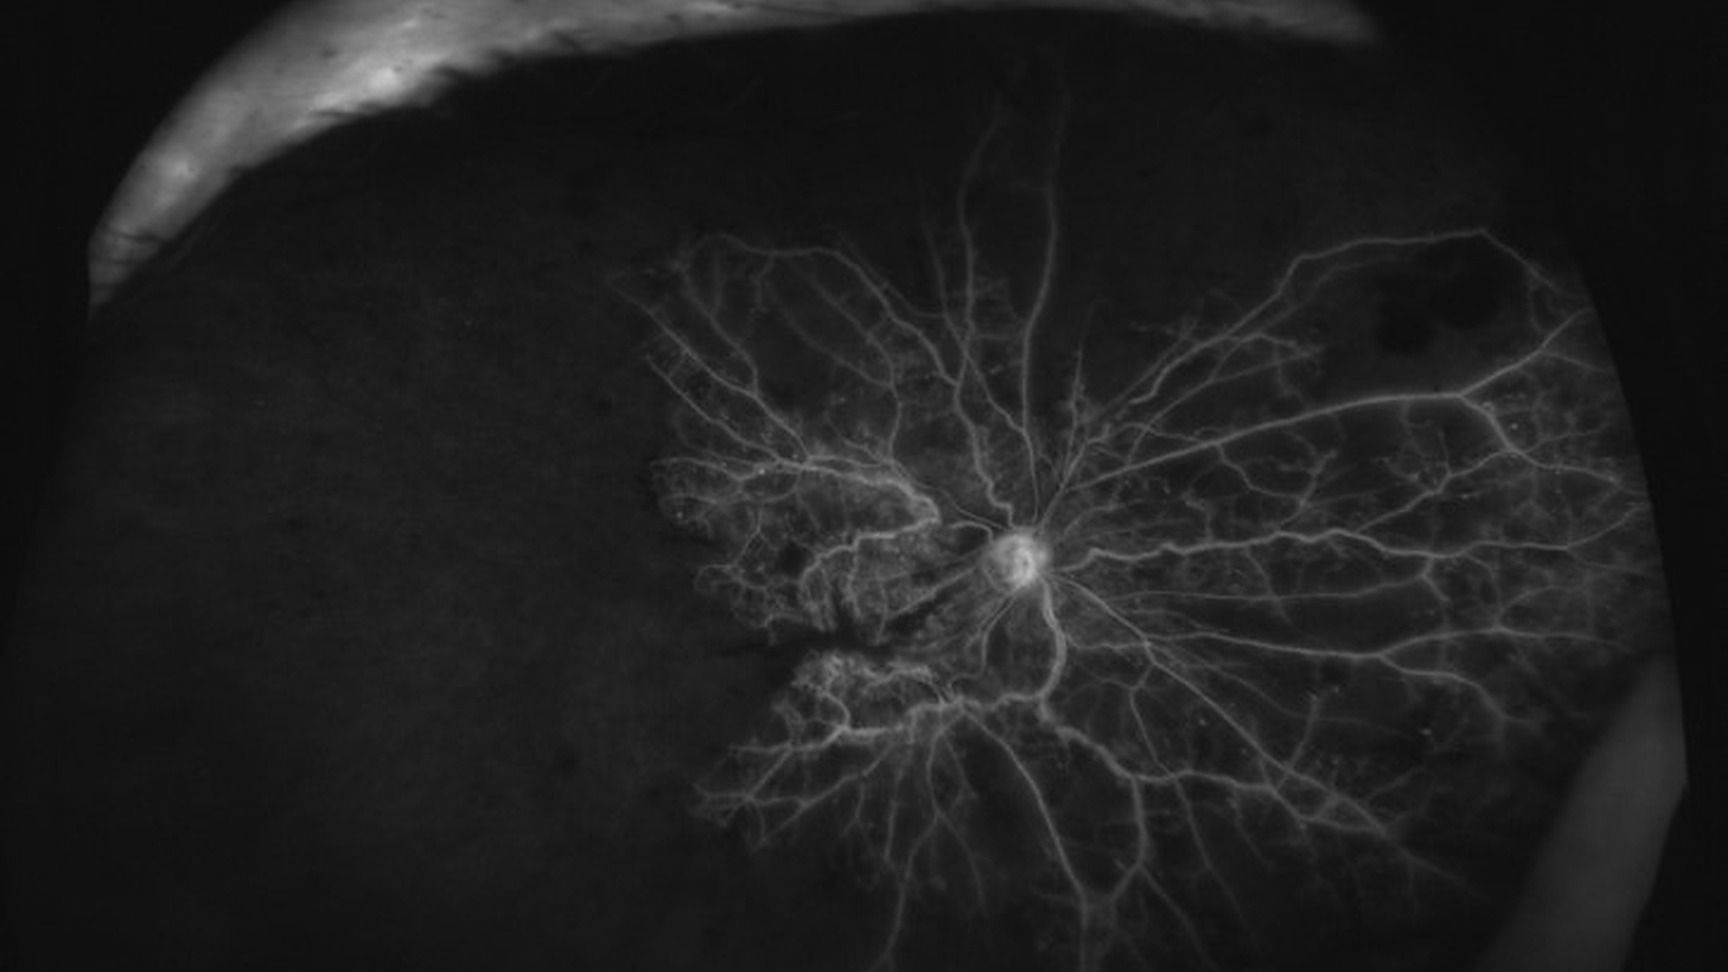

Anti-VEGF et pathologies rétiniennes (hors DMLA et diabète)

Nous connaissons depuis peu les anti-VEGF comme traitement de la dégénérescence maculaire liée à l'âge DMLA exsudative ou de la rétinopathie diabétique mais il existe d'autres indications.

En effet, dans le cadre des occlusions veineuses, ces molécules constituent l'un des traitements et il est important de connaître leur place dans la prise en charge des patients présentant ce type de pathologie.

Dans le cadre de néovaisseaux choroïdiens NVC ou d'exsudation qui ne sont pas une DMLA, par exemple les NVC du myope fort ou encore un naevus compliqué d'une néovascularisation, leurs utilisations n'est pas identiques au schéma de traitement de la DMLA. Les IVT d'anti-VEGF doivent être utilisées avec une bonne connaissance de ces pathologies afin d'éviter, parfois, des complications induites par le traitement.

Identifier les signes cliniques des OVR et connaître les modalités de prise en charge, notamment par anti-VEGF

Prendre en charge les néovaisseaux choroïdiens qui ne proviennent pas d’une DMLA (NVC du myope fort, du sujet jeune ou inflammatoire et rappeler leurs modalités de prise en charge différentes d’une DMLA

Identifier un naevus ou un hémangiome choroïdien avec une échographie avant toute injection intravitréenne IVT d’anti-VEGF

Ne pas réaliser d’IVT d’anti-VEGF sur un naevus compliqué de NVC sans concertation pluridisciplinaire